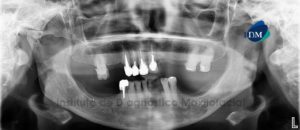

041 – Planificación y Tratamiento en Rehabilitación Oral con Prótesis sobre Implantes usando Análisis Cefalométrico

En los pacientes desdentados, que requieren una prótesis completa ya sea convencional o implanto soportada, los dientes artificiales se colocan en la prótesis completa por